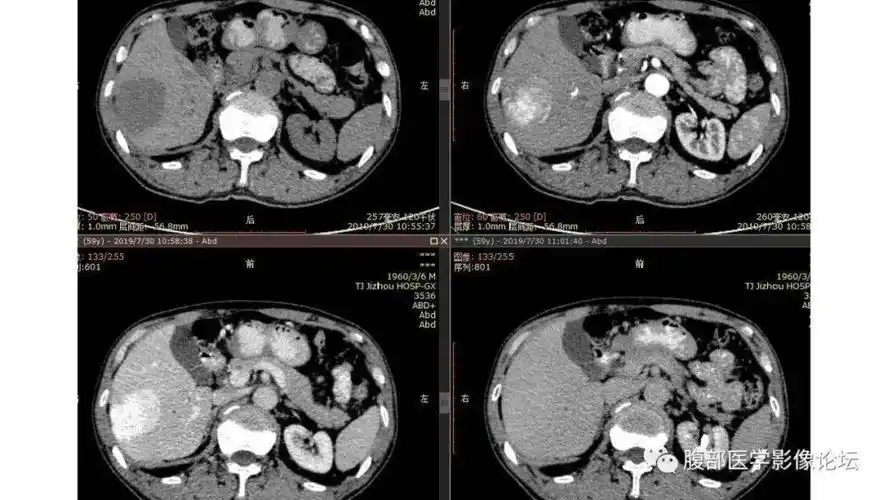

肝内多发血管瘤,求助博莱碘化油

执业医师实践技能影像学ct诊断《肝血管瘤》

(肝血管瘤的典型ct图像,肝血管瘤可以通过增强ct确诊)六,普及了这么多

肝脏血管瘤影像学表现及鉴别诊断二影像天地

肝脏血管瘤影像学表现及鉴别诊断(一) | 影像天地

ct显示肝左叶大血管瘤